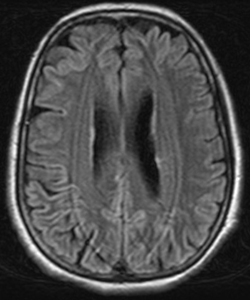

- MRI shows diffuse white matter lesions on the cerebral hemispheres, especially in the anterior temporal lobes and external capsules

With early-onset vascular dementia, there are usually lifestyle factors involved such as uncontrolled or undetected high blood pressure and an unhealthy diet. Recent scientific research has also linked high cholesterol levels with the development of vascular dementia.